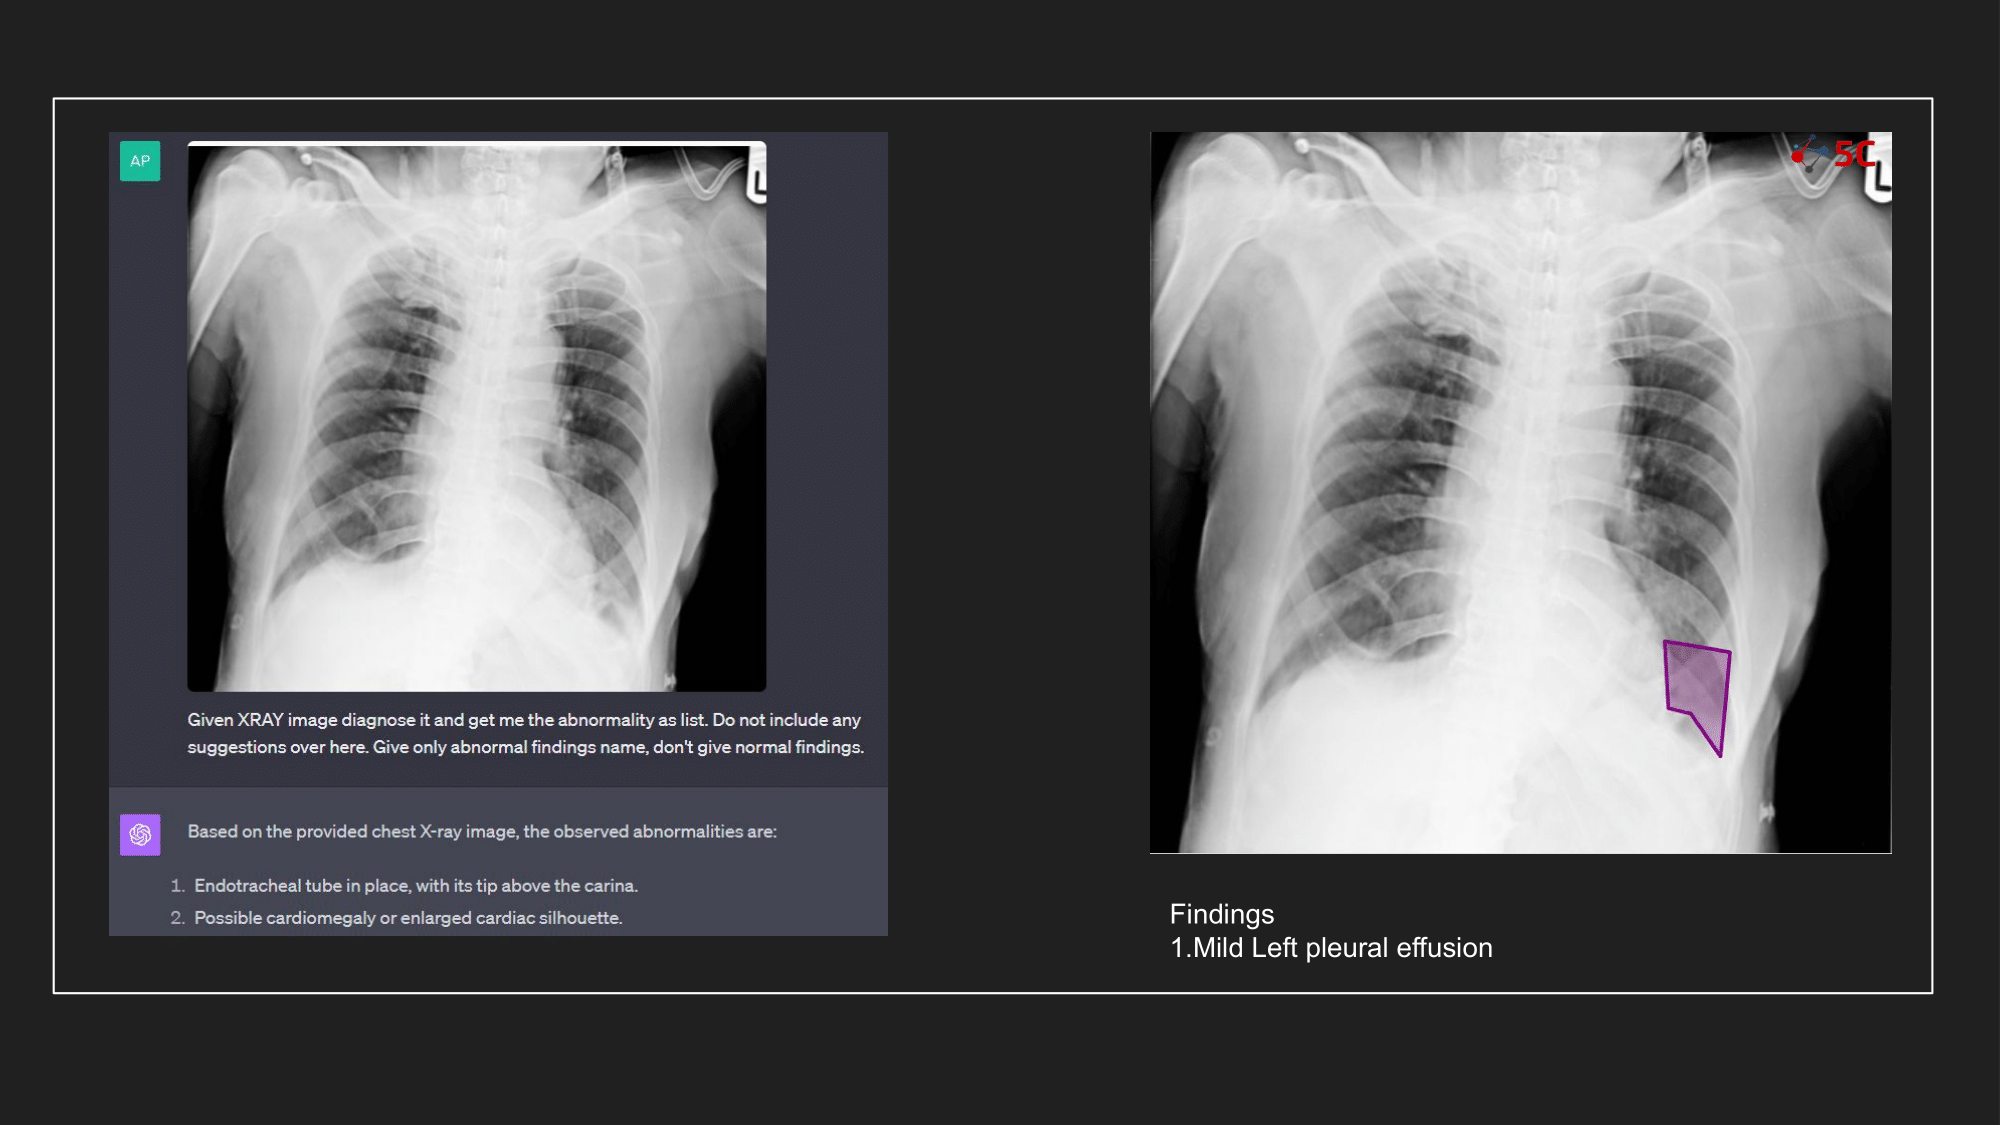

To gauge GPT-4V's prowess in detecting pleural effusion, an experiment was conducted with 10 random chest X-rays known to have pleural effusion. The XRays were sent to GPT-4V, Radiologists as well as to 5C's AI.

Presented below are the results from the experiment.

The output from GPT-4V and from 5C's AI model for the Chest XRays are provided at the end of the post.